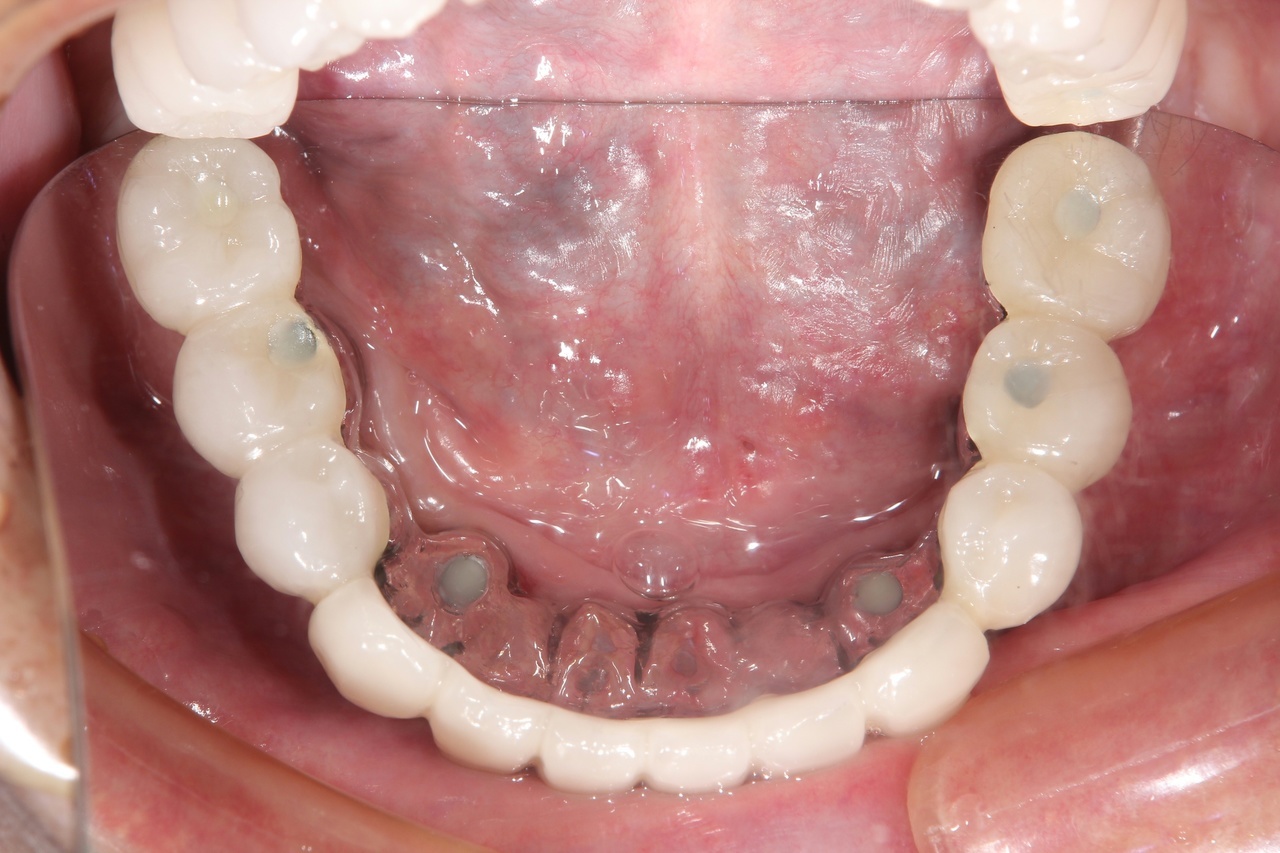

最終的な被せ物装着

インプラントがしっかり骨に定着したら、型取りをして、最終的な被せ物を製作し、装着します。

完成後のレントゲン写真

最終的な被せ物を装着した状態のレントゲン写真。

(今回は下顎ですが、その前に上顎は治療済みです。)